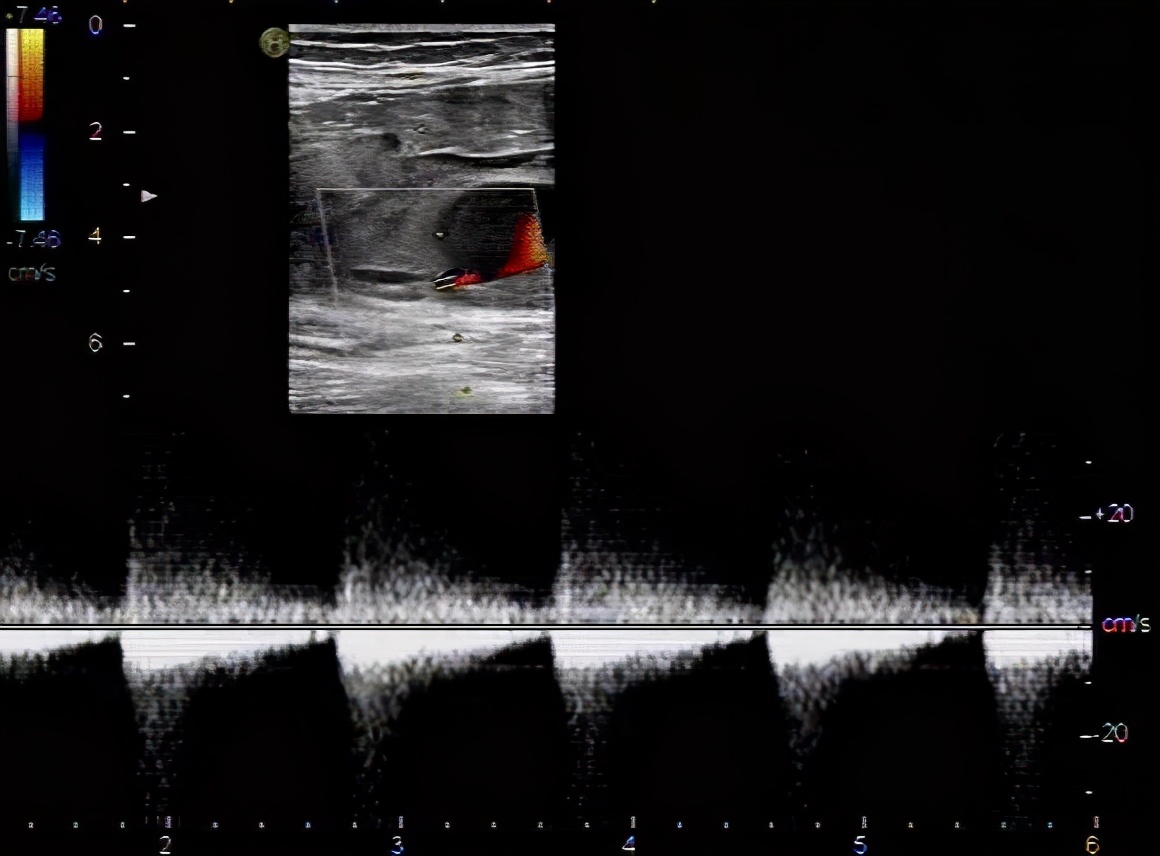

文章图片

血流呈花色涡流 , 腔内低回声考虑为血栓形成 , 超声提示:真性动脉瘤伴血栓形成 。